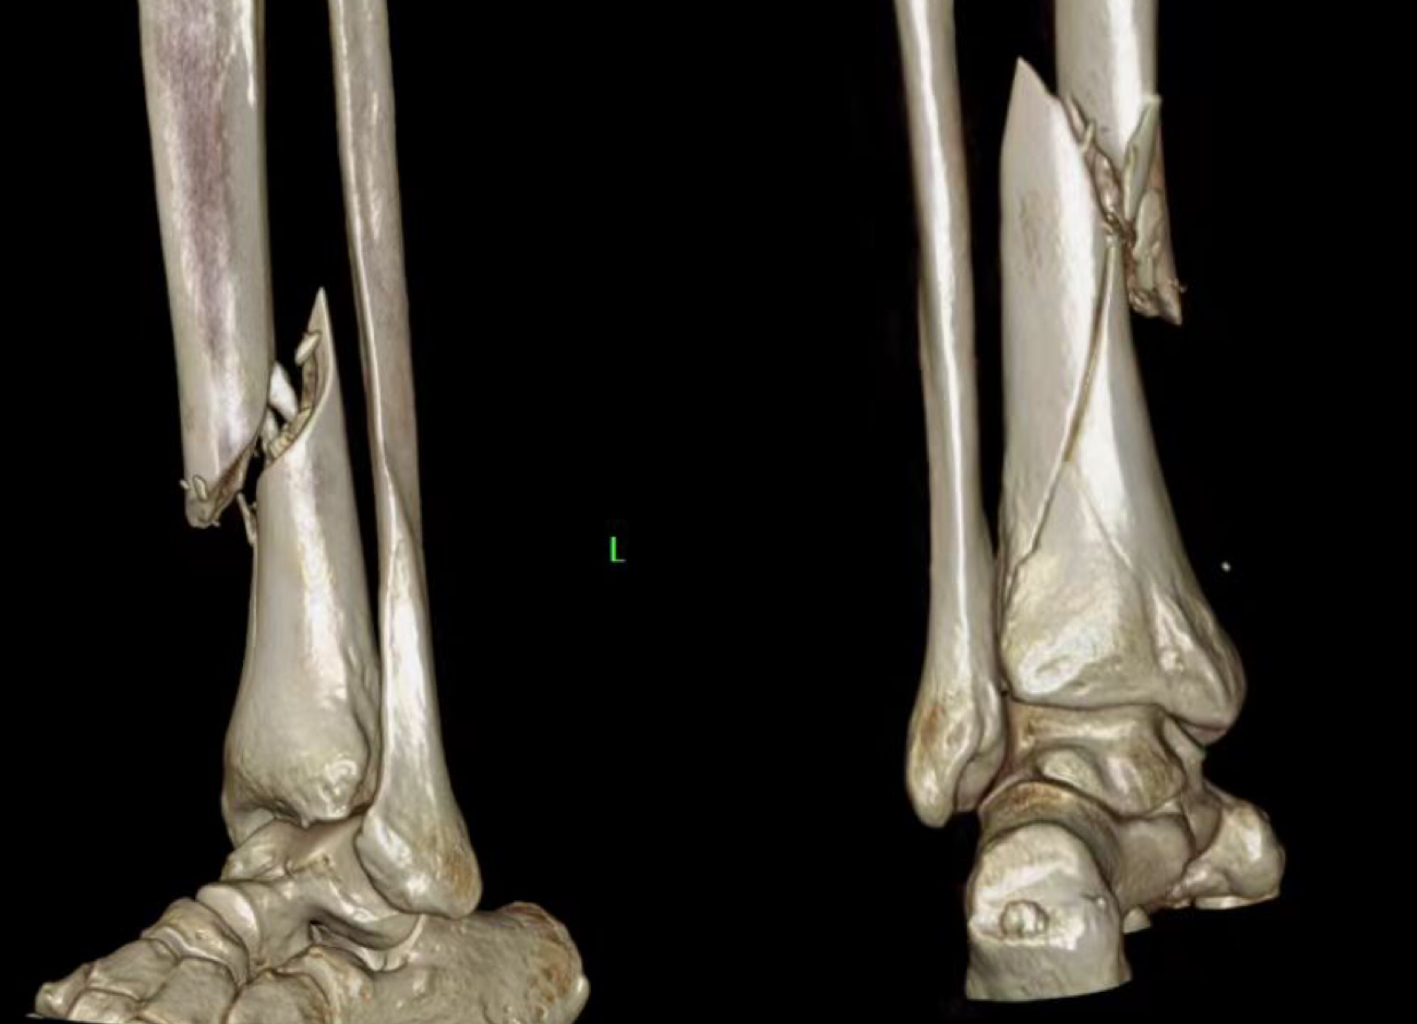

病例一:患者,女,70岁,车祸致左肱骨近端粉碎骨折,在孙院长组织术前讨论后决定行”左肱骨近端粉碎性骨折闭合复位髓内钉内固定术”考虑患者年龄大、基础病较多,微创治疗恢复快,骨三科医疗团队为其行手术治疗,术后功能恢复良好,患者及家属十分满意。 ▲术前 ▲术后 病例二:患者,男,51岁,因滑倒摔伤致左胫腓骨骨折伴后踝骨折,术前准备钢板内固定、髓内钉闭合内固定两种手术方案,通过术前讨论和局部皮肤条件的观察,选用髓内钉闭合复位内固定,骨三科医疗团队主刀下运用多枚克氏针(阻挡+固定+合拢),解决后踝和螺旋劈裂骨折块问题,手术顺利结束。 ▲术前 ▲术后 ▲术后 ▲术后微创小切口 目前,我院骨三科医疗团队已成功完成数例髓内钉手术,临床疗效非常满意。近年来周口人合医院骨三科大力发展微创技术,积极开展各类微创手术,力求打造微创以及快速康复的治疗新标杆,更好地为人民健康保驾护航。 ▲创伤与手足显微外科专家查房查看患者病情 ▲创伤与手足显微外科专家共同探讨患者病情